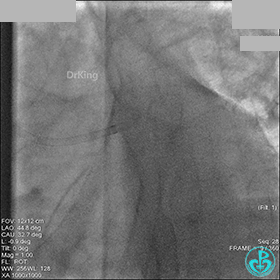

冠脉造影

入院次日冠脉造影显示粗大左主干末端中度狭窄,前降支开口严重狭窄,回旋支与前降支角度大,弥漫性长病变,严重狭窄,粗大右冠脉近中段弥漫性中重度狭窄。由于病变复杂,造影结束后先下台,择期再行介入治疗。